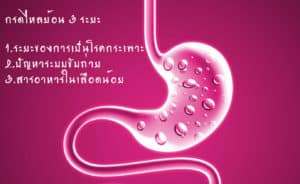

1.ตรวจเช็คว่าตัวเองเป็นกรดไหลย้อนระยะไหน เพื่อที่จะได้นำไปสู่การปฏิบัติดูแลตัวเอง และแก้ไขปัญหาได้อย่างถูกต้องเพราะแต่ละระยะแก้ปัญหาไม่เหมือนกัน กรดไหลย้อน สามารถแบ่งได้ 3 ระยะ คือ

1.ตรวจเช็คว่าตัวเองเป็นกรดไหลย้อนระยะไหน เพื่อที่จะได้นำไปสู่การปฏิบัติดูแลตัวเอง และแก้ไขปัญหาได้อย่างถูกต้องเพราะแต่ละระยะแก้ปัญหาไม่เหมือนกัน กรดไหลย้อน สามารถแบ่งได้ 3 ระยะ คือ

ระยะ1 ระยะเริ่มต้น หรือระยะโรคกระเพาะ เป็นระยะที่อาการยังไม่เยอะ เป็นระยะที่สามารถแก้ปัญหาได้ง่ายที่สุด เพราะอาการของกรดไหลย้อนยังไม่เยอะมากนัก เป็นระยะที่เพิ่งจะทราบอาการ อาการของระยะนี้จะมีอาการ เหมือนโรคกระเพาะ จะมีอาการจุกเสียด แน่นท้องบ่อยครั้ง มีลมในท้องเยอะ บางท่านอาจปวดเมื่อยตามตัว เพราะมีลมดันตามอวัยวะต่างๆ หรืออาจมีอาการเรอเปรี้ยวบ้าง แต่ยังไม่เยอะ

ระยะที่ 2 เป็นระยะที่อาการกรดไหลย้อนเริ่มมีอาการมากขึ้น และเริ่มมีปัญหาระบบขับถ่าย ระยะนี้จะมีอาการแน่นท้องจุกเสียดในท้อง และบริเวณลำคอมากขึ้น เรอเปรี้ยวมากขึ้น แน่นท้องมากขึ้น และมีปัญหาการขับถ่าย การขับถ่ายไม่ดี เพราะมีปัญหาต่อเนื่องจากการย่อยอาหารได้ไม่ดีในกระเพาะอาหาร

ระยะที่ 3 เป็นระยะที่สารอาหารในเลือดน้อย อันเนื่องจากกระเพาะอาหารมีปัญหามายาวนาน จึงไม่สามารถดูดซึมสารอาหารไปหล่อเลี้ยงร่างกายได้เพียงพอ ทำให้ร่างกายอ่อนเพลีย ง่วงนอนบ่อย นอนหลับไม่สนิท หากอาการเยอะ ก็จะทำให้น้ำหนักลด (อ่านรายละเอียดเพิ่มเติม เกี่ยวกับ กรดไหลย้อน 3 ระยะ )